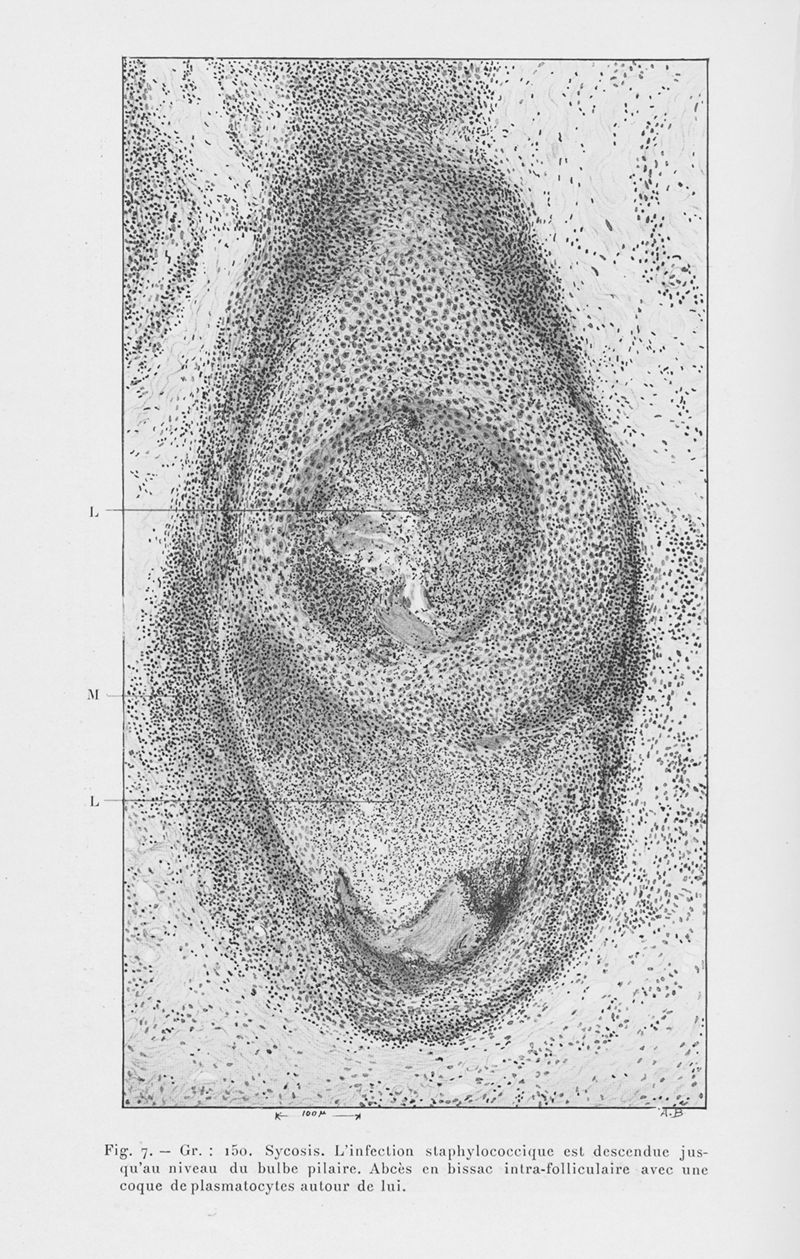

Annales de dermatologie et de syphiligraphie

6ème série, tome VII. - Paris : Masson, 1926.